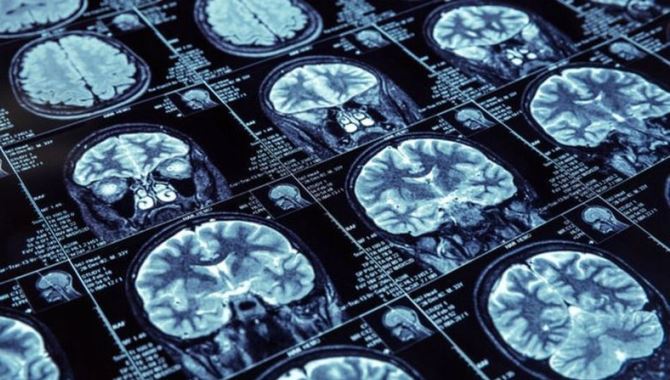

Medipol Üniversitesi'nin bünyesinde yürüttüğü akademik çalışmada, parkinson hastalarında beyin pili ile erken dönemde koku alma duyusunun geri getirildiği saptandı.

Açıklamada görüşlerine yer verilen Zırh, yapılan çalışmanın, beyin pili tedavisinin kısa dönemde koku duyusu üzerinde etkilerinin araştırıldığı en fazla vaka sayısı ile yapılmış olması ve yitirilmiş bazı fizyolojik fonksiyonların geri kazanılabilmesini ortaya koyması yönünden büyük önem arz ettiğini belirterek, Derin Beyin Stimülasyonunun parkinson hastalarında hastalığın titreme, katılık, tutukluk, yavaşlama, yürüme güçlüğü gibi motor bulguları üzerine olumlu etkiler bıraktığını ve 'hastalığın saatini geri alan' bir tedavi yöntemi olarak adlandırılabileceğini ifade etti.

Zırh, söz konusu çalışma ile beyin pili tedavisinin parkinson hastalarında, hastalığın motor bulgularını düzeltmenin yanı sıra, 3 ay gibi kısa bir süre içerisinde koku işlevini geliştirdiğini ve koku alma duyusu kaybını geri kazandırdığının ortaya konulduğunu sözlerine ekledi.

Çalışmayı yürüten ekipte yer alan Medipol Üniversitesi Nöroloji Bölümü Dr. Öğr. Üyesi Nesrin Helvacı Yılmaz ise "Koku duyusu kaybı parkinson hastalarında, hastalığın erken evrelerinde gözlemlenen ve hatta hastalık başlamadan yıllar önce ortaya çıkan bir bulgudur. Çalışmamızda parkinson hastalığında Derin Beyin Stimülasyonu (DBS-Beyin Pili Yerleştirilmesi) yapılmış 45 hastada 3 ay içinde koku fonksiyonlarında, motor bulgulardan bağımsız olarak düzelme olduğunu tespit ettik." değerlendirmesinde bulundu.

Yılmaz, bu çalışma ışığında DBS operasyonlarının sadece anatomik ve fizyolojik yapılarda düzelme sağlamadığını aynı zamanda hücre düzeyinde de bir yenilenmeye neden olduğunu düşündürdüğünü dile getirdi.